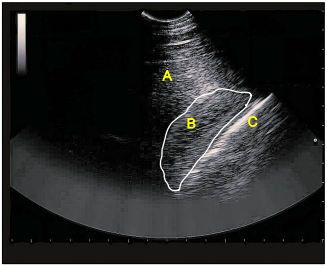

A avaliação ultrassonográfica abdominal adquiriu grande importância e foi incorporada ao protocolo de exame admissional de cavalos com abdome agudo.

Enunciado 4509945-1

Na ultrassonografia, identifique as estruturas anatômicas abdominais observadas na imagem e assinale a alternativa correta.